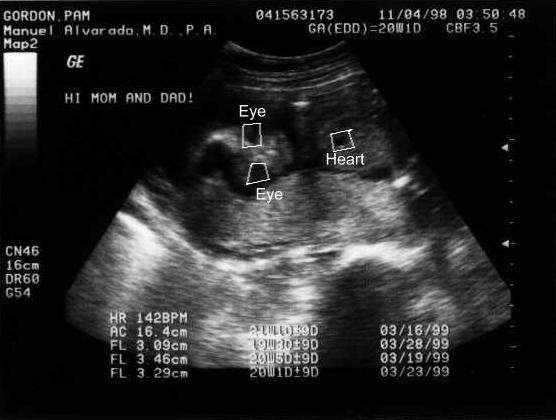

My Ultrasound Pictures!!